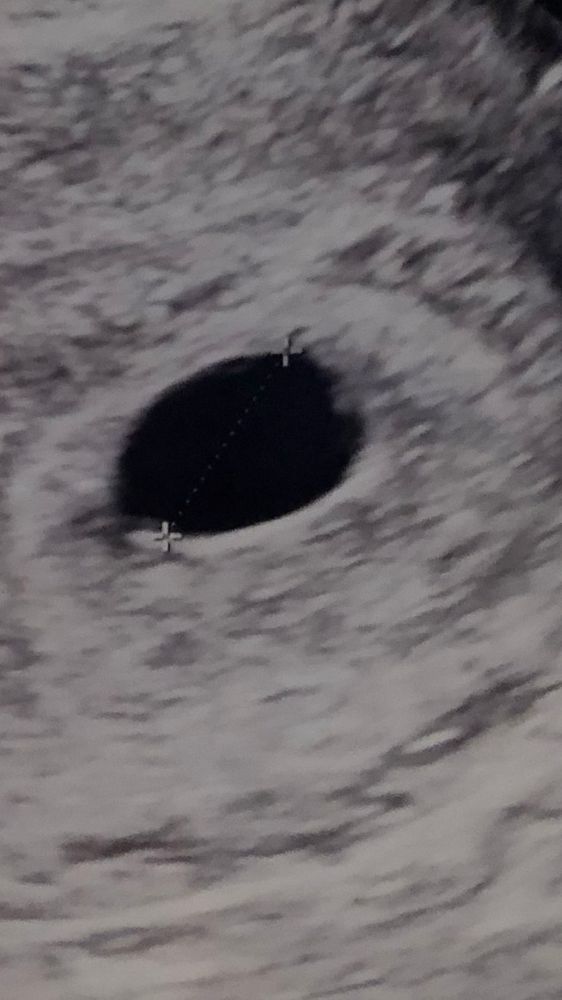

Здравствуйте. Девочки…6 акушерских недель. Сделала узи. Узистка ничего не увидела..хгч сдала один раз. Срок по хгч 4-5 недель. Вы что-то видите?

Если у вас 9мм яйцо, то это же очень мало еще. Анэмбрионию ставят если при 25мм пусто. А я у вас вижу справа что-то маленькое, похожее на желточный мешочек. Через недельку переделайте узи

Анэмбрионию ставят если в пя 15 мм,нет жм или с жм,но без без эмбриона в пя 25 мм,у вас ещё пя маловато,через неделю повторно сходите,уже должно всё быть,у меня в пя 8 мм,жм был всего 1,6 мм,на фото я его вообще у себя не разглядела,но врач в протоколе указала,был бы чуть хуже аппарат могли не разглядеть

На 4-5 нед может быть ещё ничего не видно кроме ПЯ, после 5 недели уже должны увидеть желточный мешок

Муся, яйцо 8-9 мм. Акушерские 6. Т.е по факту 4-5 недель. Хгч на 4-5 недель. Все работает по узи: сосуды, желтое тело 23мм. Грудь налитая, чувствительная. Мочевой в шоке…бегаю в туалет..